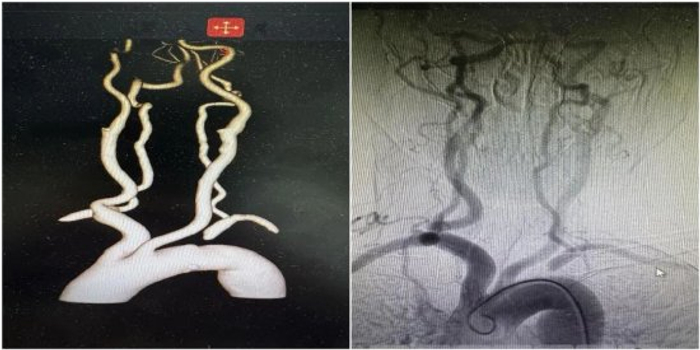

入院后,进行了头颈部CTA及全脑血管造影术(DSA),进一步证实了判断——张女士左侧锁骨下动脉起始段完全闭塞。正是这根血管的堵塞,导致血液无法顺利流向左侧上肢和脑部后循环,反而通过左侧椎动脉从大脑里“偷”血,从而引发了严重的头晕和上肢缺血症状。

(头颈部血管CTA检查提示左侧锁骨下动脉起始段完全闭塞)